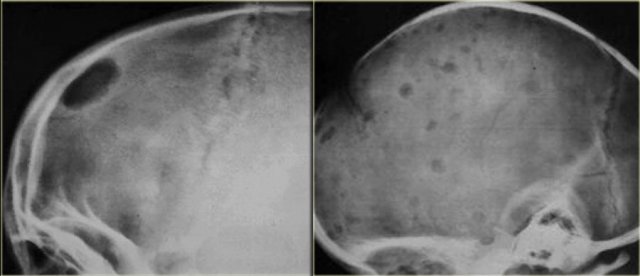

Eosinophilic granuloma (3)

On the left a well-defined osteolytic lesion.

A zone of sclerosis can be seen surrounding the lytic lesion.

Sometimes a so called button-sequestrum is found in the central part.

The case on the right shows multiple ill-defined lesions in the parietal and frontal bone.

Histology revealed eosiniphilic granuloma.

In a young child with multiple lytic lesions of the neurocranium EG is the most likely diagnosis.